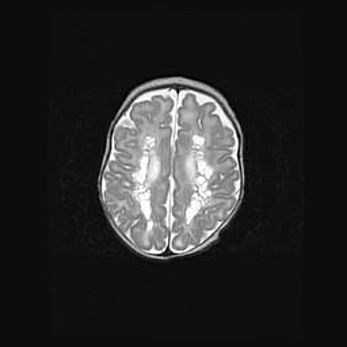

Лейкомаляция с кистозно-глиозной дегенерацией головного мозга.

Возраст: 2 месяца 25 дней

Вес: 6400 г

Окружность головы: 40 см

Срок гестации: 41 неделя

Лейкомаляцию относят к ишемически-гипоксическим повреждениям головного мозга, диагностируемым у новорожденных. При лейкомаляции в головном мозге обнаруживают очаги некроза, возникшие после тяжелой гипоксии и нарушения кровотока. В процессе морфогенеза очаги проходят три стадии: 1) развития некроза, 2) резорбции и 3) формирования глиозного рубца или кисты. Перивентрикулярная лейкомаляция (ПЛ) встречается примерно в 12% случаев среди новорожденных, обычно – у недоношенных детей, причем, частота ее зависит от массы, с которой младенец появился на свет. Наибольшее число малышей страдает лейкомаляцией, если масса при рождении 1500-2500 г.